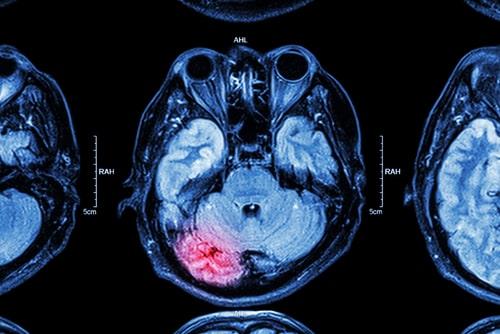

In recent years, there has been increasing awareness of the dangers that professional athletes face due to the high risk of serious brain injury. The risk is heightened if you play a sport with a higher chance of repeated trauma to the head, like in hockey, wrestling, and football for example. The repeated hits to the head suffered by someone who has been playing a particular sport professionally for several years can lead to the development of what is known as chronic traumatic encephalopathy (CTE), which can result in severe disability. If a loved one suffered brain trauma that developed into CTE, speak with a knowledgeable Naperville, IL personal injury attorney with experience in similar cases to understand how to move forward.

CTE is linked to repeated head trauma, and professional athletes are among the groups with the highest risk of developing it. This disease often gets worse over time and can even lead to dementia. There are four main stages of CTE, with the symptoms associated with these stages generally appearing between eight and ten years after the repetitive brain trauma. The stages are:

Unfortunately, there is no way to diagnose CTE during one’s life and no cure for it. There are tests that can be performed to diagnose CTE, but only during an autopsy. This makes the disease even more devastating. Not only is there no way to get better, but there is also nothing to help you or your loved one understand what is happening and why they are acting the way they are.